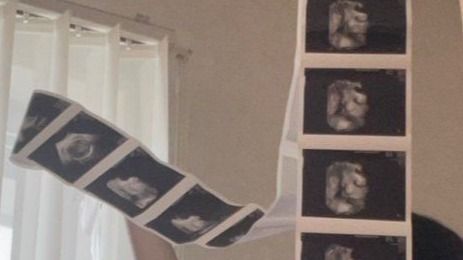

ずらぁぁと撮影されたカットがつながっています。数えてみると…少なくとも10枚以上!

お母さんは、両手を使ってエコー写真を持っていますが、あまりの長さのためか、途中で折らないと見せられない状態になっていました。

そして、第2子を撮影したエコー写真はというと…

天井の高さまで伸びた15枚以上のエコー写真が!椅子に乗って撮影していますが、見切れているところも。